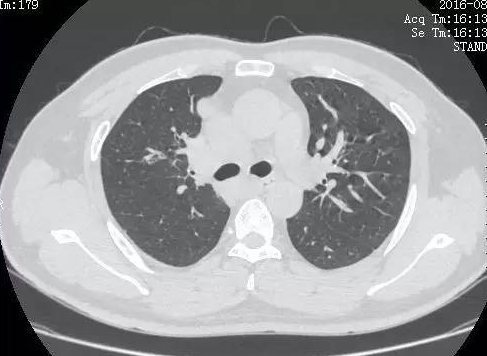

小細胞肺癌CT成像

多數癌症只要是早期發現,治療的效果都比較理想。但某些癌症本身發生很快,甚至像小細胞肺癌一樣會出現早期轉移,這樣就給早期發現製造了很多困難。目前職工體檢的胸部X線攝片能夠發現比相對較大的肺內病灶,如果是惡性度低、進展緩慢的非小細胞肺癌,就不算發現得晚。但如果是惡性度比較高的肺癌,發展到胸透能發現的大小時往往就比較晚了。

尤其是小細胞肺癌,肺內的原發灶可能很小,甚至胸透一直無法發現。直到出現骨轉移出現骨痛,或者腦轉移引起慢性頭痛才被注意到。所以體檢常做的X線平片對於發現肺癌確實有積極意義,但對於肺癌之王恐怕就不夠靈敏了。

這時候低劑量胸部CT就派上用場了,這種檢查的放射劑量比傳統CT更低,但對微小病灶的識別力更強。能夠有助於肺癌的早期發現。曾經滬上某知名三甲醫院的胸外科主任在醫院引進低劑量CT掃描的時候自己去體驗了一把,發現了直徑僅5毫米的早期肺癌病灶,從而躺在自家醫院的手術枱上接受手術,着實是“撿回了一條命”,被傳為佳話。